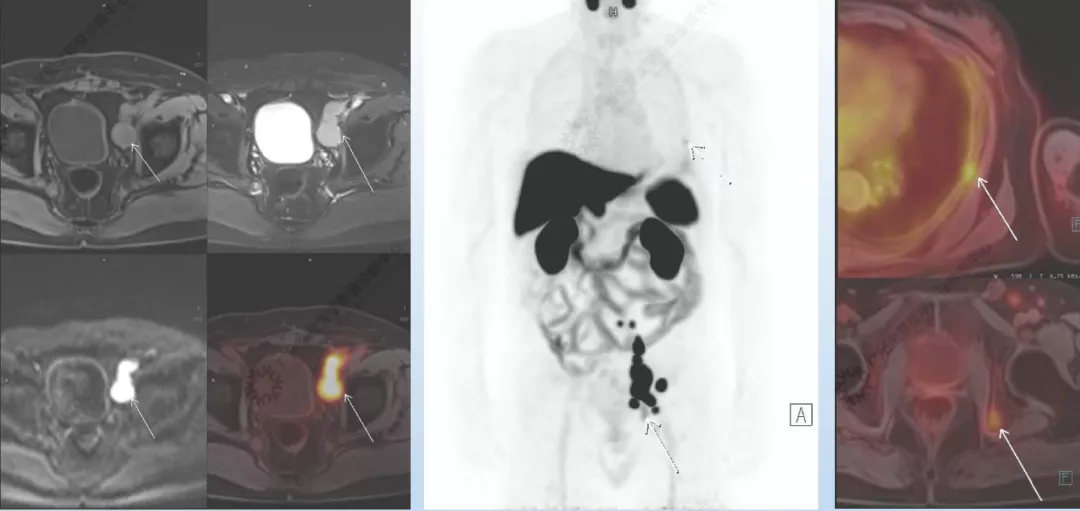

2. 《18F-PSMA靶向PET/MRI成像技术在前列腺癌中的应用价值》 汇报人曾玉萍

从MRI的优势及不足、PET/MR特点、前列腺特异性膜抗原等几个方向进行讲解,并例举案例辅助说明。

案例展示: